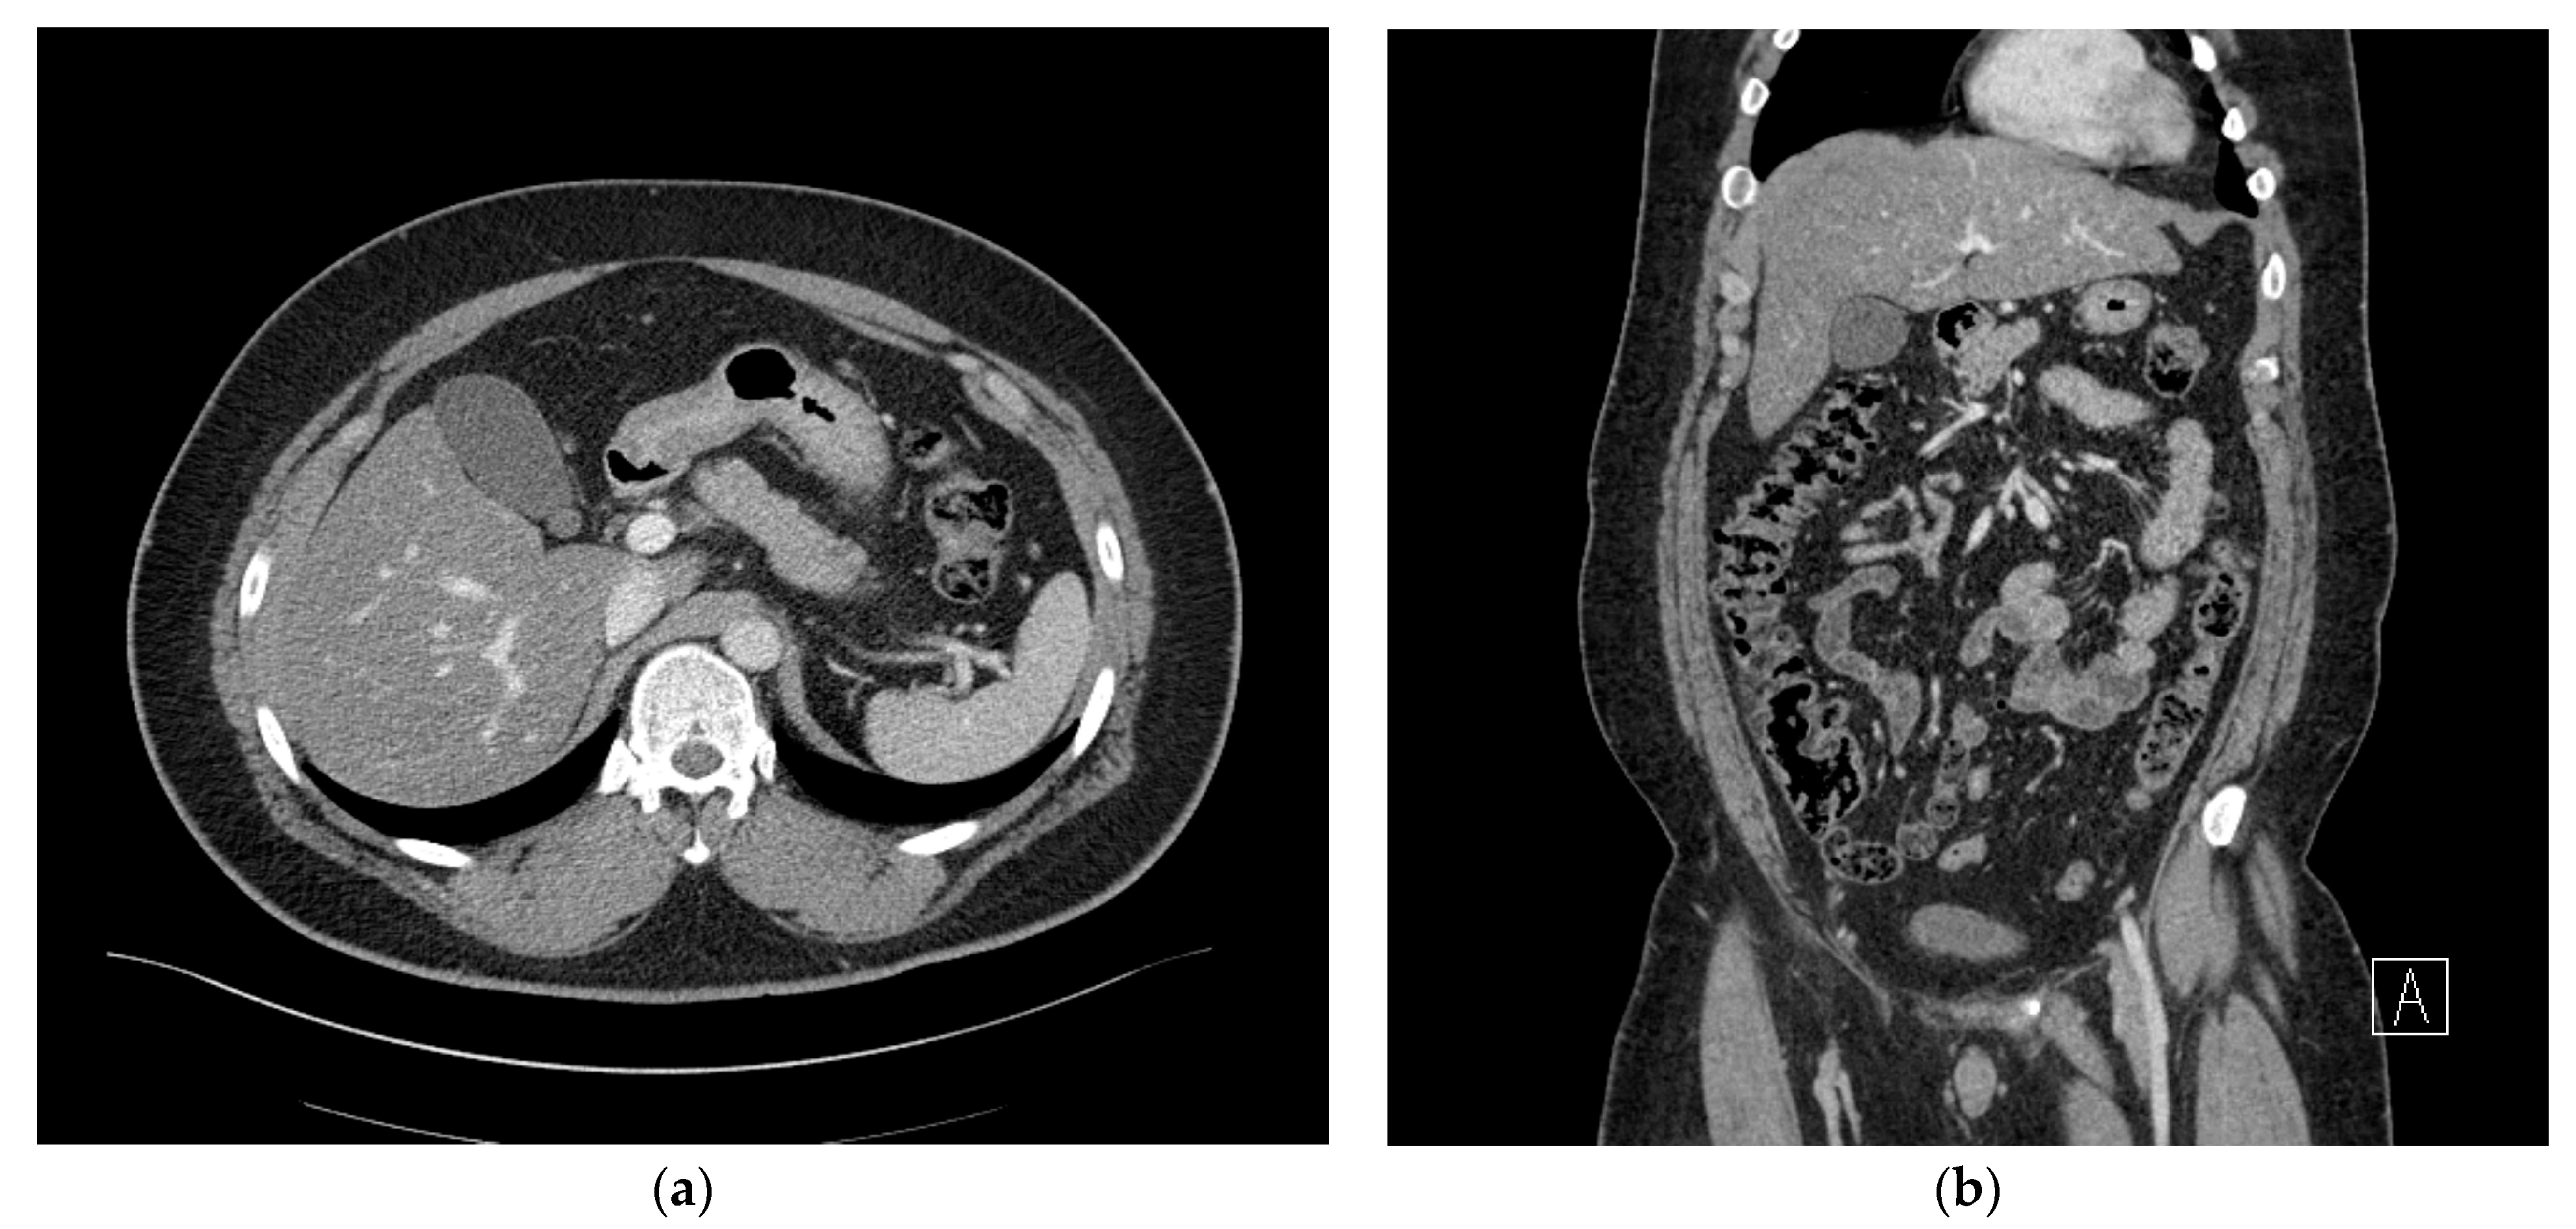

2. Case Presentation